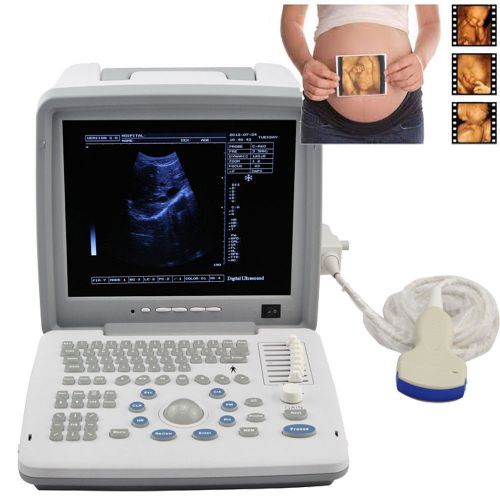

US $1,000.00

Brand | Denshine |

| Output interface | 2 SVGA video outputs | ||

| MPN | Does Not Apply | ||

| Output interface 1 | SVGA color monitor circumscribed | ||

| Screen | 12-inch SVGA high resolution monitor | ||

| Output interface 2 | 2 PAL video outputs | ||

| technology | Full digital imaging technology | ||

| Probes optional | convex linear transvaginal rectal | ||

| software | abundant built-in software packages | ||

| equipment potional | printer trolly | ||

| probe connectors | two | ||

| Approved | CE FDA | ||

| 3D | 3D Ultrasound image working station |

12.1 CE LED Full Digital Portable Ultrasound Scanner + convex + 3D workstation